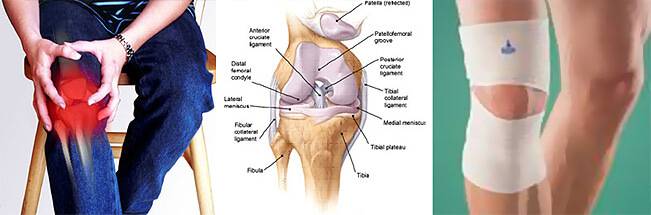

Фото и диагностика кисты Бейкера